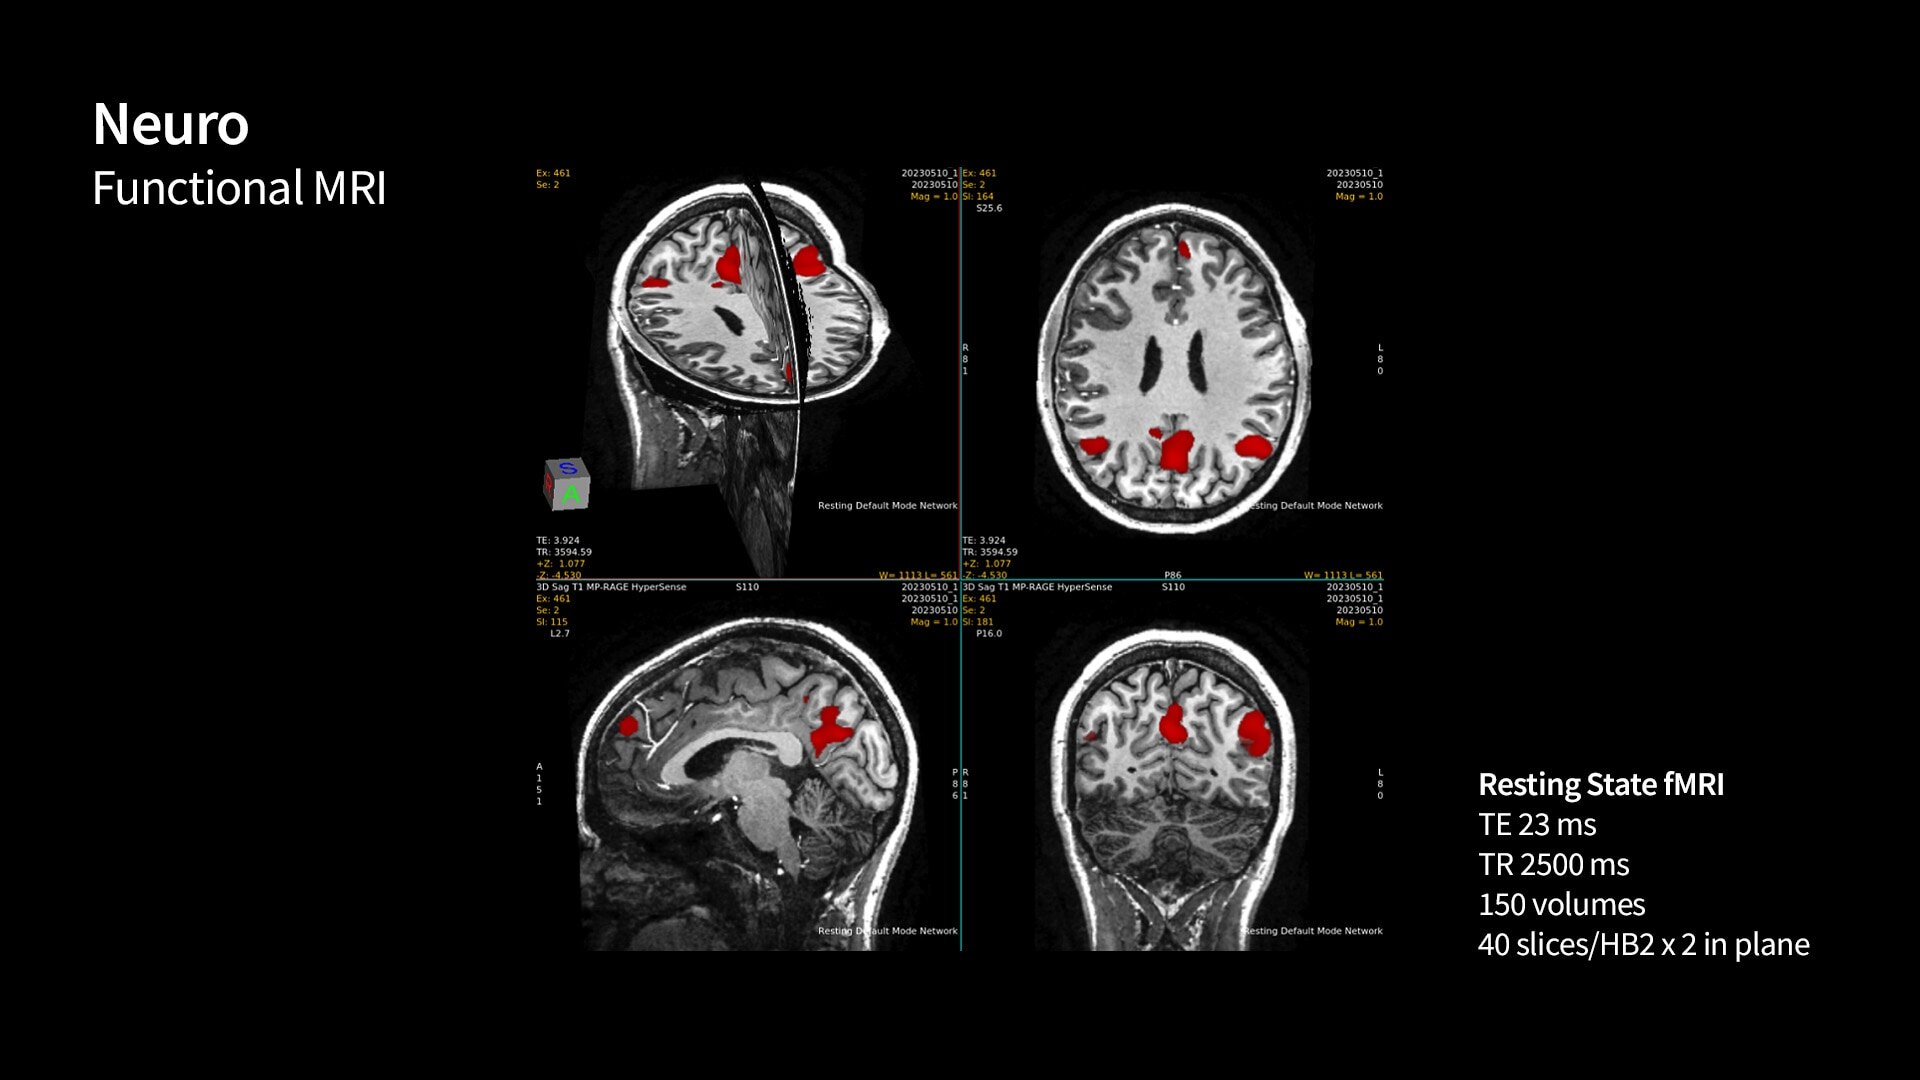

Uncover new contrasts, such as Quantitative Susceptibility Mapping (QSM), for advancing neurological disorder research. Explore novel biomarkers for ischemic stroke characterization and uncover subtle structures with ultra-high resolution imaging with our SIGNA 7T platform.

SIGNA 7T powered by a common suite of SIGNA Imaging Applications

Users have access to our latest state-of-the-art applications along with deep-learning tools like AIR x™ Brain and Knee as well as AIR™ Recon DL, while delivering the diagnostic confidence of an ultra-high-field system.